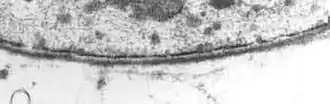

![]() Transmission electron micrograph displaying basal lamina that is lining the external surface of cell membrane. | |

The basal lamina is a layer of extracellular matrix secreted by the epithelial cells, on which the epithelium sits. It is often incorrectly referred to as the basement membrane, though it does constitute a portion of the basement membrane. The basal lamina is visible only with the electron microscope, where it appears as an electron-dense layer that is 20–100 nm thick (with some exceptions that are thicker, such as basal lamina in lung alveoli and renal glomeruli).